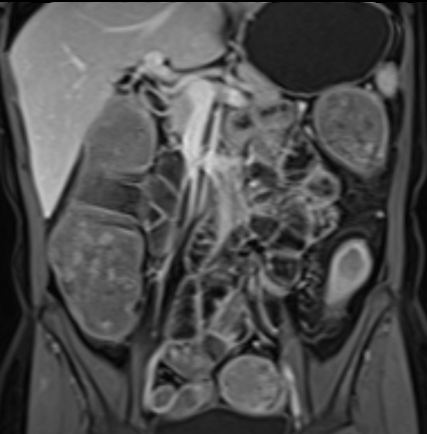

Bệnh nhân nữ 48 tuổi, đang điều trị bằng thuốc kháng TNF, được chỉ định nội soi đại tràng.

Phát hiện hẹp lòng ruột ở đại tràng sigma, không thể vượt qua được khi nội soi.

MR-enterography được thực hiện để đánh giá mức độ lan rộng của chỗ hẹp.

Ruột non bình thường, nhưng ghi nhận các đoạn hẹp ở đại tràng xuống và đại tràng ngang.

Cả hai đoạn hẹp đều có thành ruột dày đến 8 mm và ngấm thuốc rõ rệt theo kiểu niêm mạc ở đại tràng xuống và kiểu phân lớp ở đại tràng ngang.

Giãn ruột trước chỗ hẹp được ghi nhận ở cả hai đoạn.

Do các chỗ hẹp này không hiện diện khi nội soi đại tràng trước khi điều trị kháng TNF, nhiều khả năng chúng đã hình thành trong quá trình điều trị.

Do đó, quyết định phẫu thuật cắt đại tràng gần toàn bộ với miệng nối hồi-sigma đã được đưa ra.